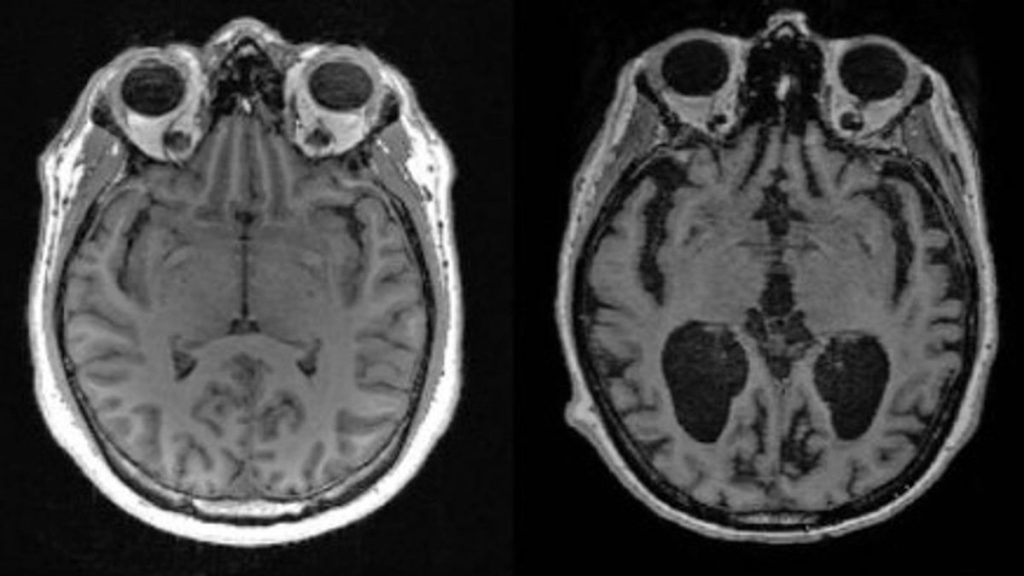

Científicos de la Facultad de Medicina de Harvard descubrieron que la pérdida de litio en el cerebro humano es uno de los primeros cambios que conducen al Alzheimer, mientras que en ratones, una depleción similar de litio aceleraba el deterioro de la memoria.

Décadas de estudios han demostrado que la enfermedad de Alzheimer implica una serie de anomalías cerebrales, entre las que se encuentran los cúmulos de la proteína beta amiloide, los embrollos de la proteína tau y la pérdida de la proteína protectora del cerebro REST.

Sin embargo, estas anomalías nunca han explicado del todo la enfermedad.

Por ejemplo, sigue sin estar claro por qué algunas personas con alteraciones cerebrales similares a las del Alzheimer nunca llegan a desarrollar demencia o deterioro cognitivo.